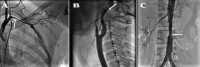

Authors describe the case of a 16-year-old girl who presented with fever, tonic-clonic seizures, unequal arm blood pressures and pulselessness in the left upper limb. On examination, there was a systolic bruit over umbilical region, a pansystolic murmur of mitral regurgitation was found. Neurological examination was normal except for an asymmetry in brain hemicircumference one side compared with the other. She has borderline intelligence (IQ 70) according to Wechsler Adult Performance Intelligence Scale. Magnetic resonance imaging (MRI) of brain revealed atrophic of left cerebral hemisphere with mildly ventricular dilatation, prominent paranasal and mastoid air cells, suggestive of Dyke-Davidoff-Masson syndrome (DDMS). Conventional angiography showed narrowed left internal carotid artery. There was also stenosed brachial artery, absent left renal artery with narrowed infrarenal abdominal aorta. The patient was put on antihypertensive drugs. We hypothesise that Takayasu arteritis and related vascular occlusion is the cause of her acquired cerebral changes.